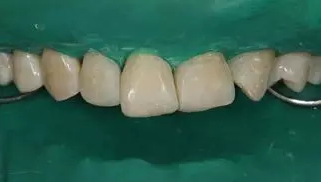

5.牙體微預(yù)備:放置橡皮障,再次確認(rèn)硅橡膠背板就位良好后,11,12,21,23 使用金剛砂車針輕輕打磨一層厚度約 0.1mm,切忌對整個(gè)唇面進(jìn)行打磨。

病例分享|復(fù)合樹脂微創(chuàng)美學(xué)修復(fù)關(guān)閉上前牙間隙

牙體微預(yù)備